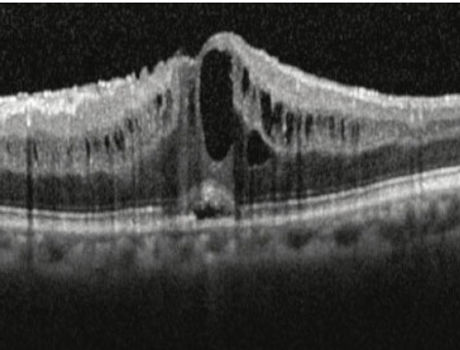

Macular hole on OCT

Cystoid macular edema on OCT